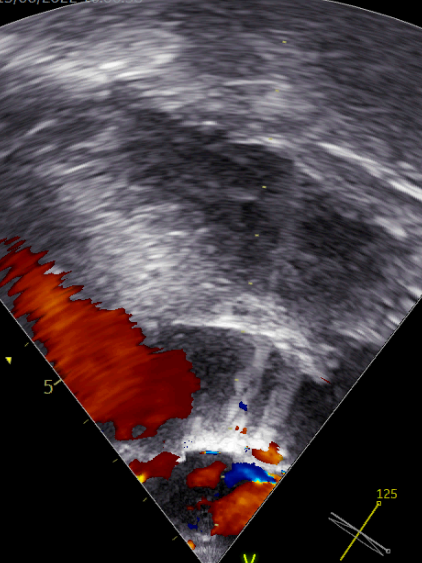

DSA显示无瓣周漏